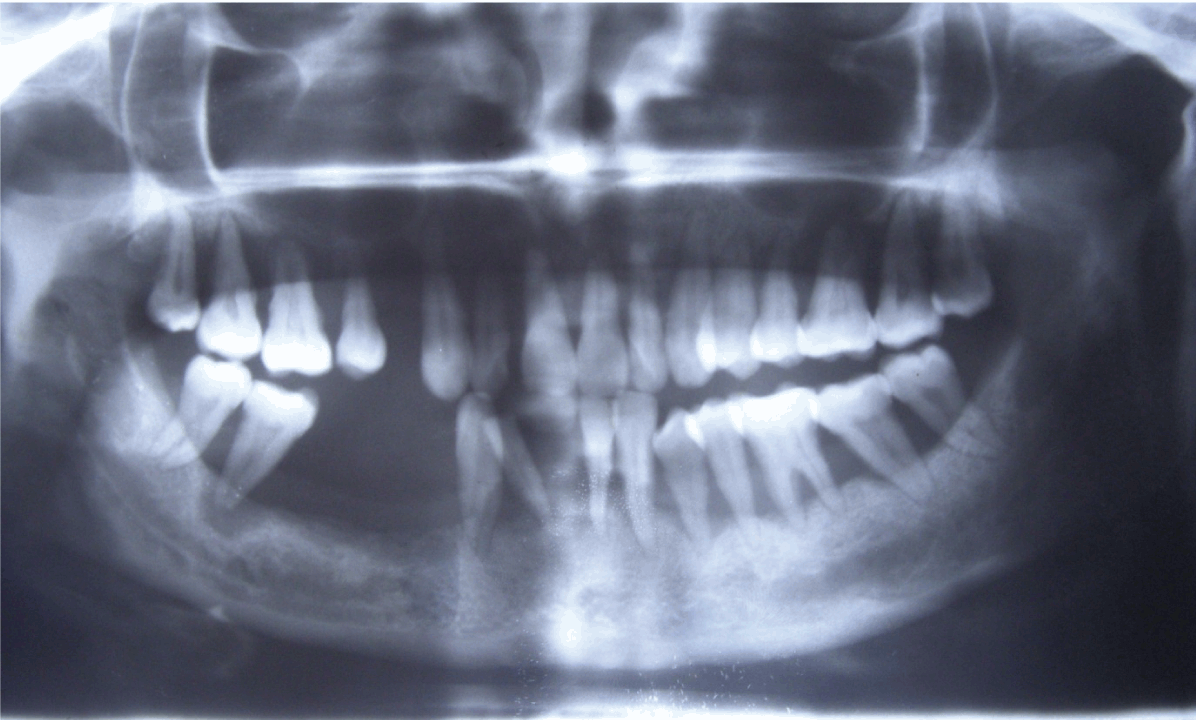

Orthopantomogram revealed severe horizontal bone loss around all the teeth. Bone loss was greater than apical third of the roots of all the teeth. Grade III furcation i.r.t 16, 26 and grade IV furcation 47. (Figure 3) Blood investigations showed normal values except for erythrocyte sedimentation rate (ESR) which was high. A biopsy was obtained, Histopathologic features showed parakeratinized stratified epithelium with elongated tube like reteridges. Epithelium over the connective tissue papillae was thinned with the proximity of the vascularized stromal tissue. Intense pooling of chronic inflammatory cells was evident suggestive of psoriasis. (Figure 4)

Cursor on image to zoom/Click text to open image

Figure 3: Orthopantomogram showing severe horizontal bone lors around all the teeth.